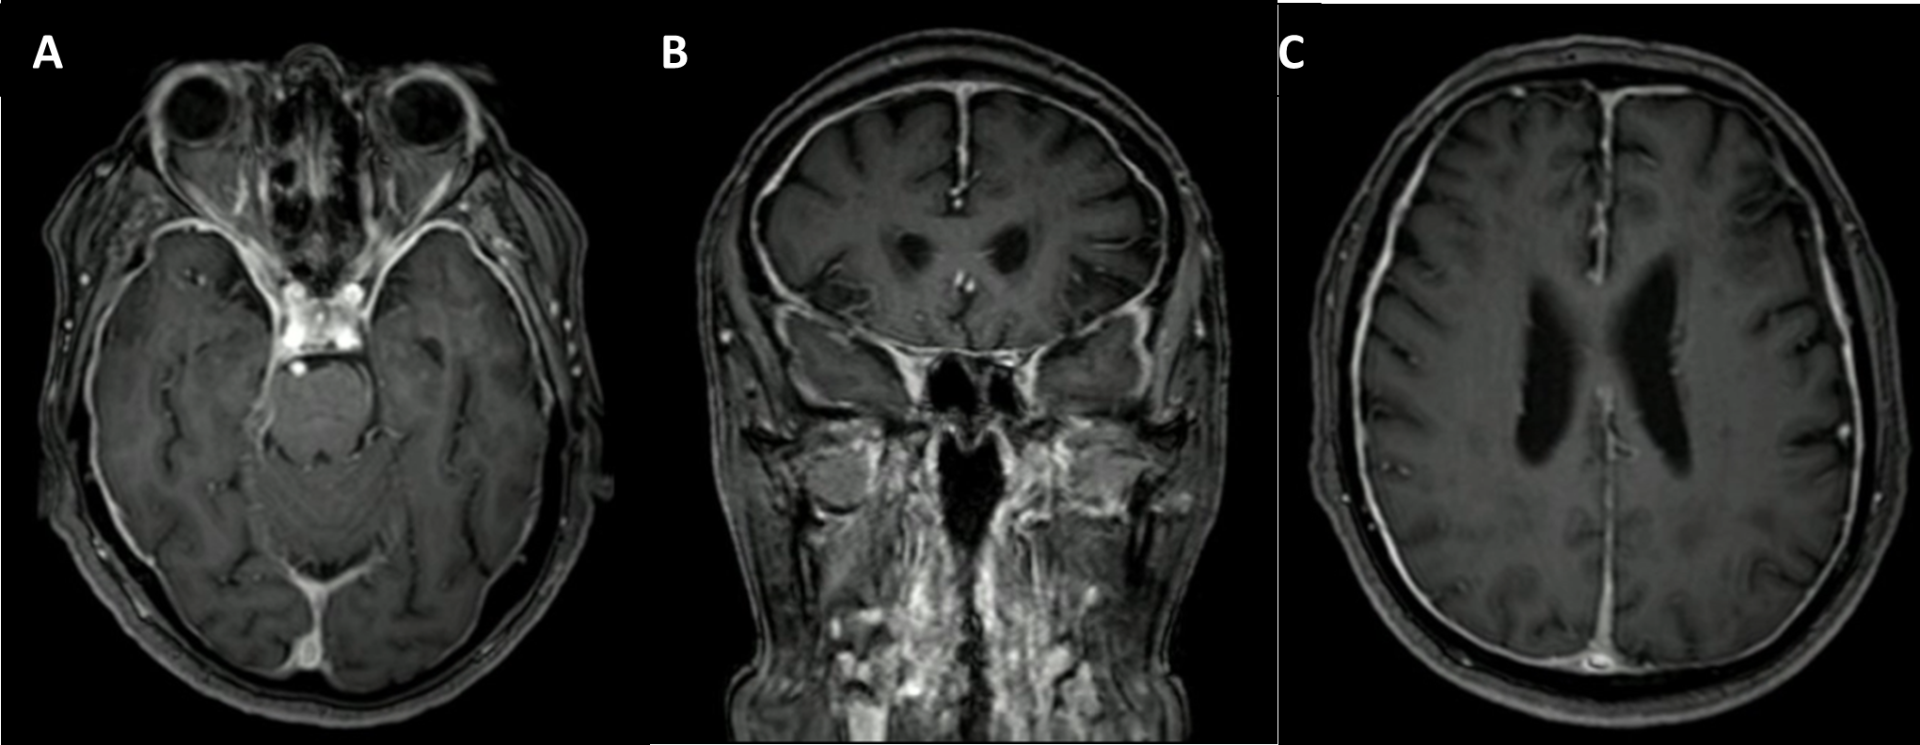

Se realizó resonancia cerebral con gadolinio que muestra paquimeningitis difusa de predominio supratentorial (Imagen 1), punción lumbar con pleocitosis (15 células) linfocitaria (98%), hiperproteinorraquia (92 mg/dl), sin hipoglucorraquia, perfil infeccioso negativo, citología y citometría de flujo negativos. Anticuerpos anti-MPO (p-ANCA) fueron positivos, sin embargo, sin cumplir criterios para vasculitis asociada a ANCA, y estudio con inmunoglobulinas séricas incluyendo IgG4, las cuales fueron normales. Se realizó además biopsia meníngea que mostró marcado engrosamiento y fibrosis con denso infiltrado linfoplasmocitario y células gigantes multinucleadas, sin observarse granulomas, y la inmunohistoquímica mostró IgG4 positiva en 124 células plasmáticas por lo que se consideró paquimeningitis por IgG4. Recibió manejo con pulsos de metilprednisolona, y se continúo manejo con azatioprina y prednisolona ambulatorias con mejoría progresiva de la cefalea y la agudeza visual, en plan de iniciarse rituximab.

Imagen 1. RM cerebral con Gadolinio: Engrosamiento liso y realce meníngeo dural difuso de predominio en la región supratentorial, involucrando la región de los canales óticos con posible compresión leve de los nervios, en corte axial (A y C) y coronal (B).